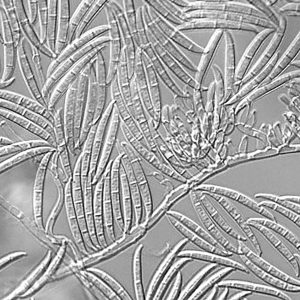

行动中蛋白质组学的一个有趣的例子是人类真菌病原体的表征Cryptococcus neoformans.,这在免疫功能低下的个体中最常与感染有关。从历史上看,研究c . neoformans依赖于更成熟的技术,比如基因组分析。然而,质谱分析和生物信息学工具和数据库的最新进展为了解真菌在感染过程中使用的生物过程提供了更多的机会,如蛋白质的释放或分泌。蛋白质组学还提供了对疾病至关重要的调节机制的见解。

鉴于抗真菌菌株的产生不断增长c . neoformans,了解更多关于响应独特环境的蛋白质的更多信息为开发替代治疗路线铺平了道路。Geddes-Mcalister博士最近曾描述过准备的有用方法c . neoformans样品和设计方案用于蛋白质组的分析变化。这提供了未来研究的基础,进一步接受这项工作,一天导致更深入地了解如何以及为什么在整个真菌感染过程中的改变。